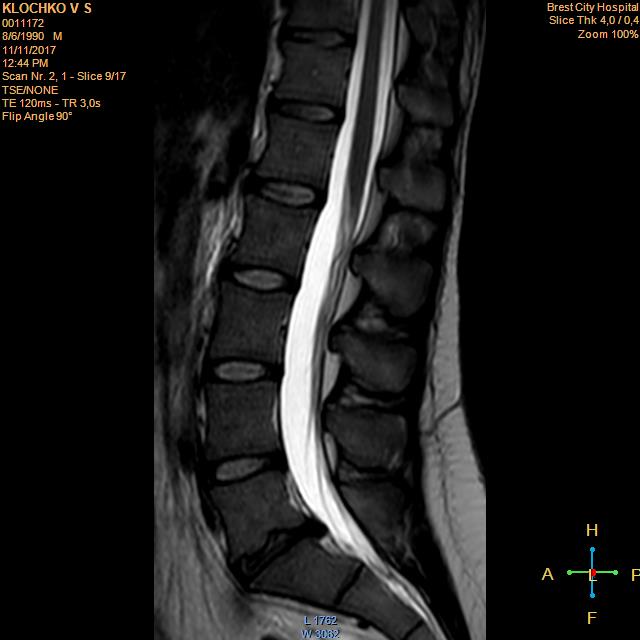

Тренировки с межпозвоночной грыжей.